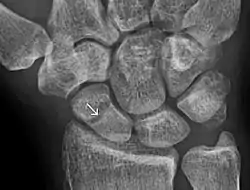

- ↑ Jarraya, Mohamed; Hayashi, Daichi; Roemer, Frank W.; Crema, Michel D.; Diaz, Luis; Conlin, Jane; Marra, Monica D.; Jomaah, Nabil; Guermazi, Ali (2013). "Radiographically Occult and Subtle Fractures: A Pictorial Review". Radiology Research and Practice. 2013: 1–10. doi:10.1155/2013/370169. ISSN 2090-1941. PMC 3613077. PMID 23577253. CC-BY 3.0